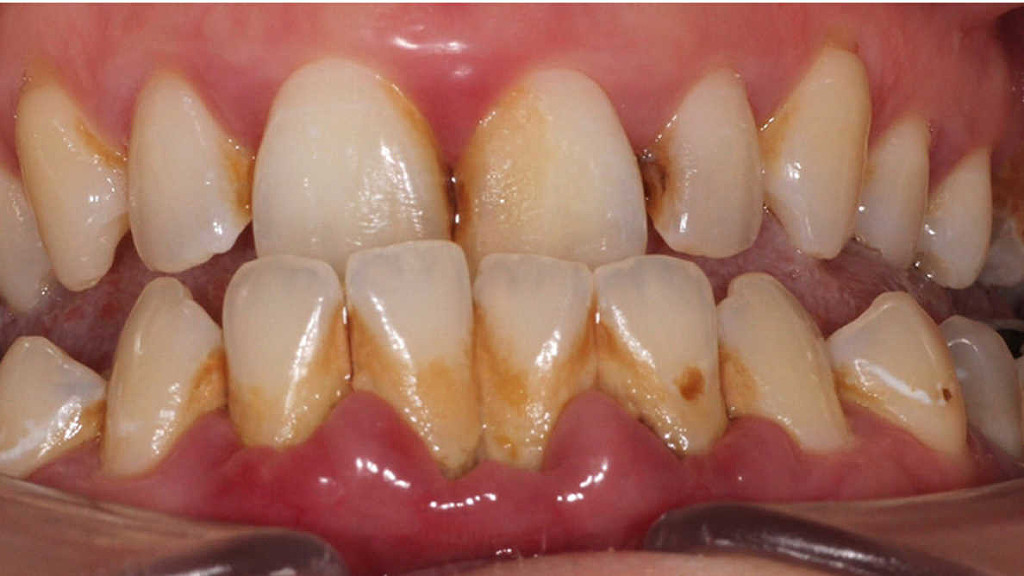

Oral biofilms, a concern for all dental professionals

Biofilms are a collective of one or more types of microorganisms that can grow on many different surfaces. Microorganisms that form biofilms include bacteria, fungi and protists.

One common example of a biofilm dental plaque, a slimy buildup of bacteria that forms on the surfaces of teeth. Pond scum is another example. Biofilms have been found growing on minerals and metals. They have been found underwater, underground and above the ground. They can grow on plant tissues and animal tissues, and on implanted medical devices such as catheters and pacemakers.

Oral biofilm is medically important because it has broad implications for maintaining not only oral health but also systemic health. It is estimated that biofilms account for over 80% of microbial infections in the body. Research has undoubtedly shown that biofilm-dependent infections, including oral diseases such as caries, and periodontal and endodontic disease, thus pose major public health and cost concerns globally.

Periodontal disease, in particular, is considered one of the most prevalent diseases worldwide, affecting up to 50% of the world’s adult population, according to FDI World Dental Federation. Previous research has established connections between periodontal disease and preterm births, low birthweight, diabetes, and risk factors associated with cardiovascular disease and stroke. Globally, periodontitis is responsible for an estimated US$54 billion per year in lost productivity and a major portion of the US$442 billion spent annually on oral disease, according to the European Federation of Periodontology.